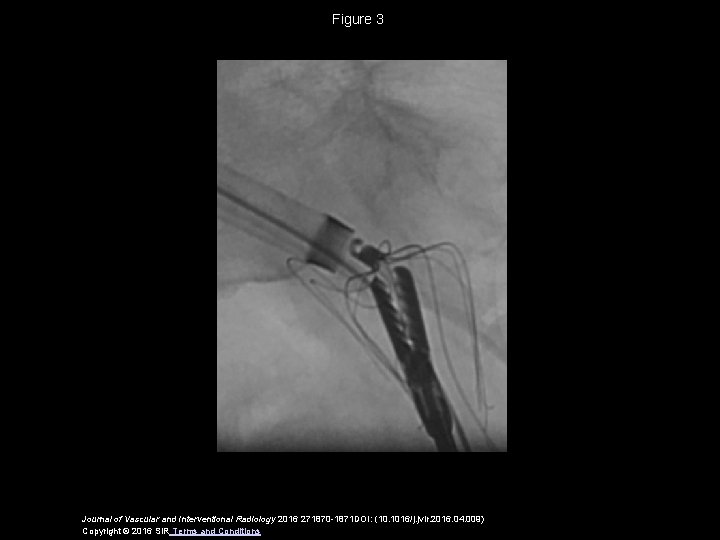

Figure 3 Journal of Vascular and Interventional Radiology 2016 271870 -1871 DOI: (10. 1016/j.

Figure 3 Journal of Vascular and Interventional Radiology 2016 271870 -1871 DOI: (10. 1016/j. jvir. 2016. 04. 009) Copyright © 2016 SIR Terms and Conditions